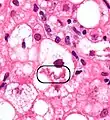

A small quantity of tissue is sampled from the liver when doing a biopsy, which is then examined under a microscope

Micrograph of non-alcoholic fatty liver disease, demonstrating marked steatosis (fat in liver cells appears white; connective tissue, blue). Trichrome stain

A liver biopsy (tissue examination) is the only test widely accepted (gold standard) as definitively diagnosing and distinguishing NAFLD (including NAFL and NASH) from other forms of liver disease and can be used to assess the severity of the inflammation and resultant fibrosis. However, since most people affected by NAFLD are likely to be asymptomatic, liver biopsy presents too high a risk for routine diagnosis, so other methods are preferred, such as liver ultrasonography or liver MRI. For young people, guidelines recommend liver ultrasonography, but biopsy remains the best evidence.[4][6][62][26] Liver biopsy is also the gold standard to detect hepatic fibrosis and assess its progression.[65] Routine liver function blood tests are not sensitive enough to detect MAFLD, and biopsy is the only procedure that can reliably differentiate NAFL from NASH.[15]